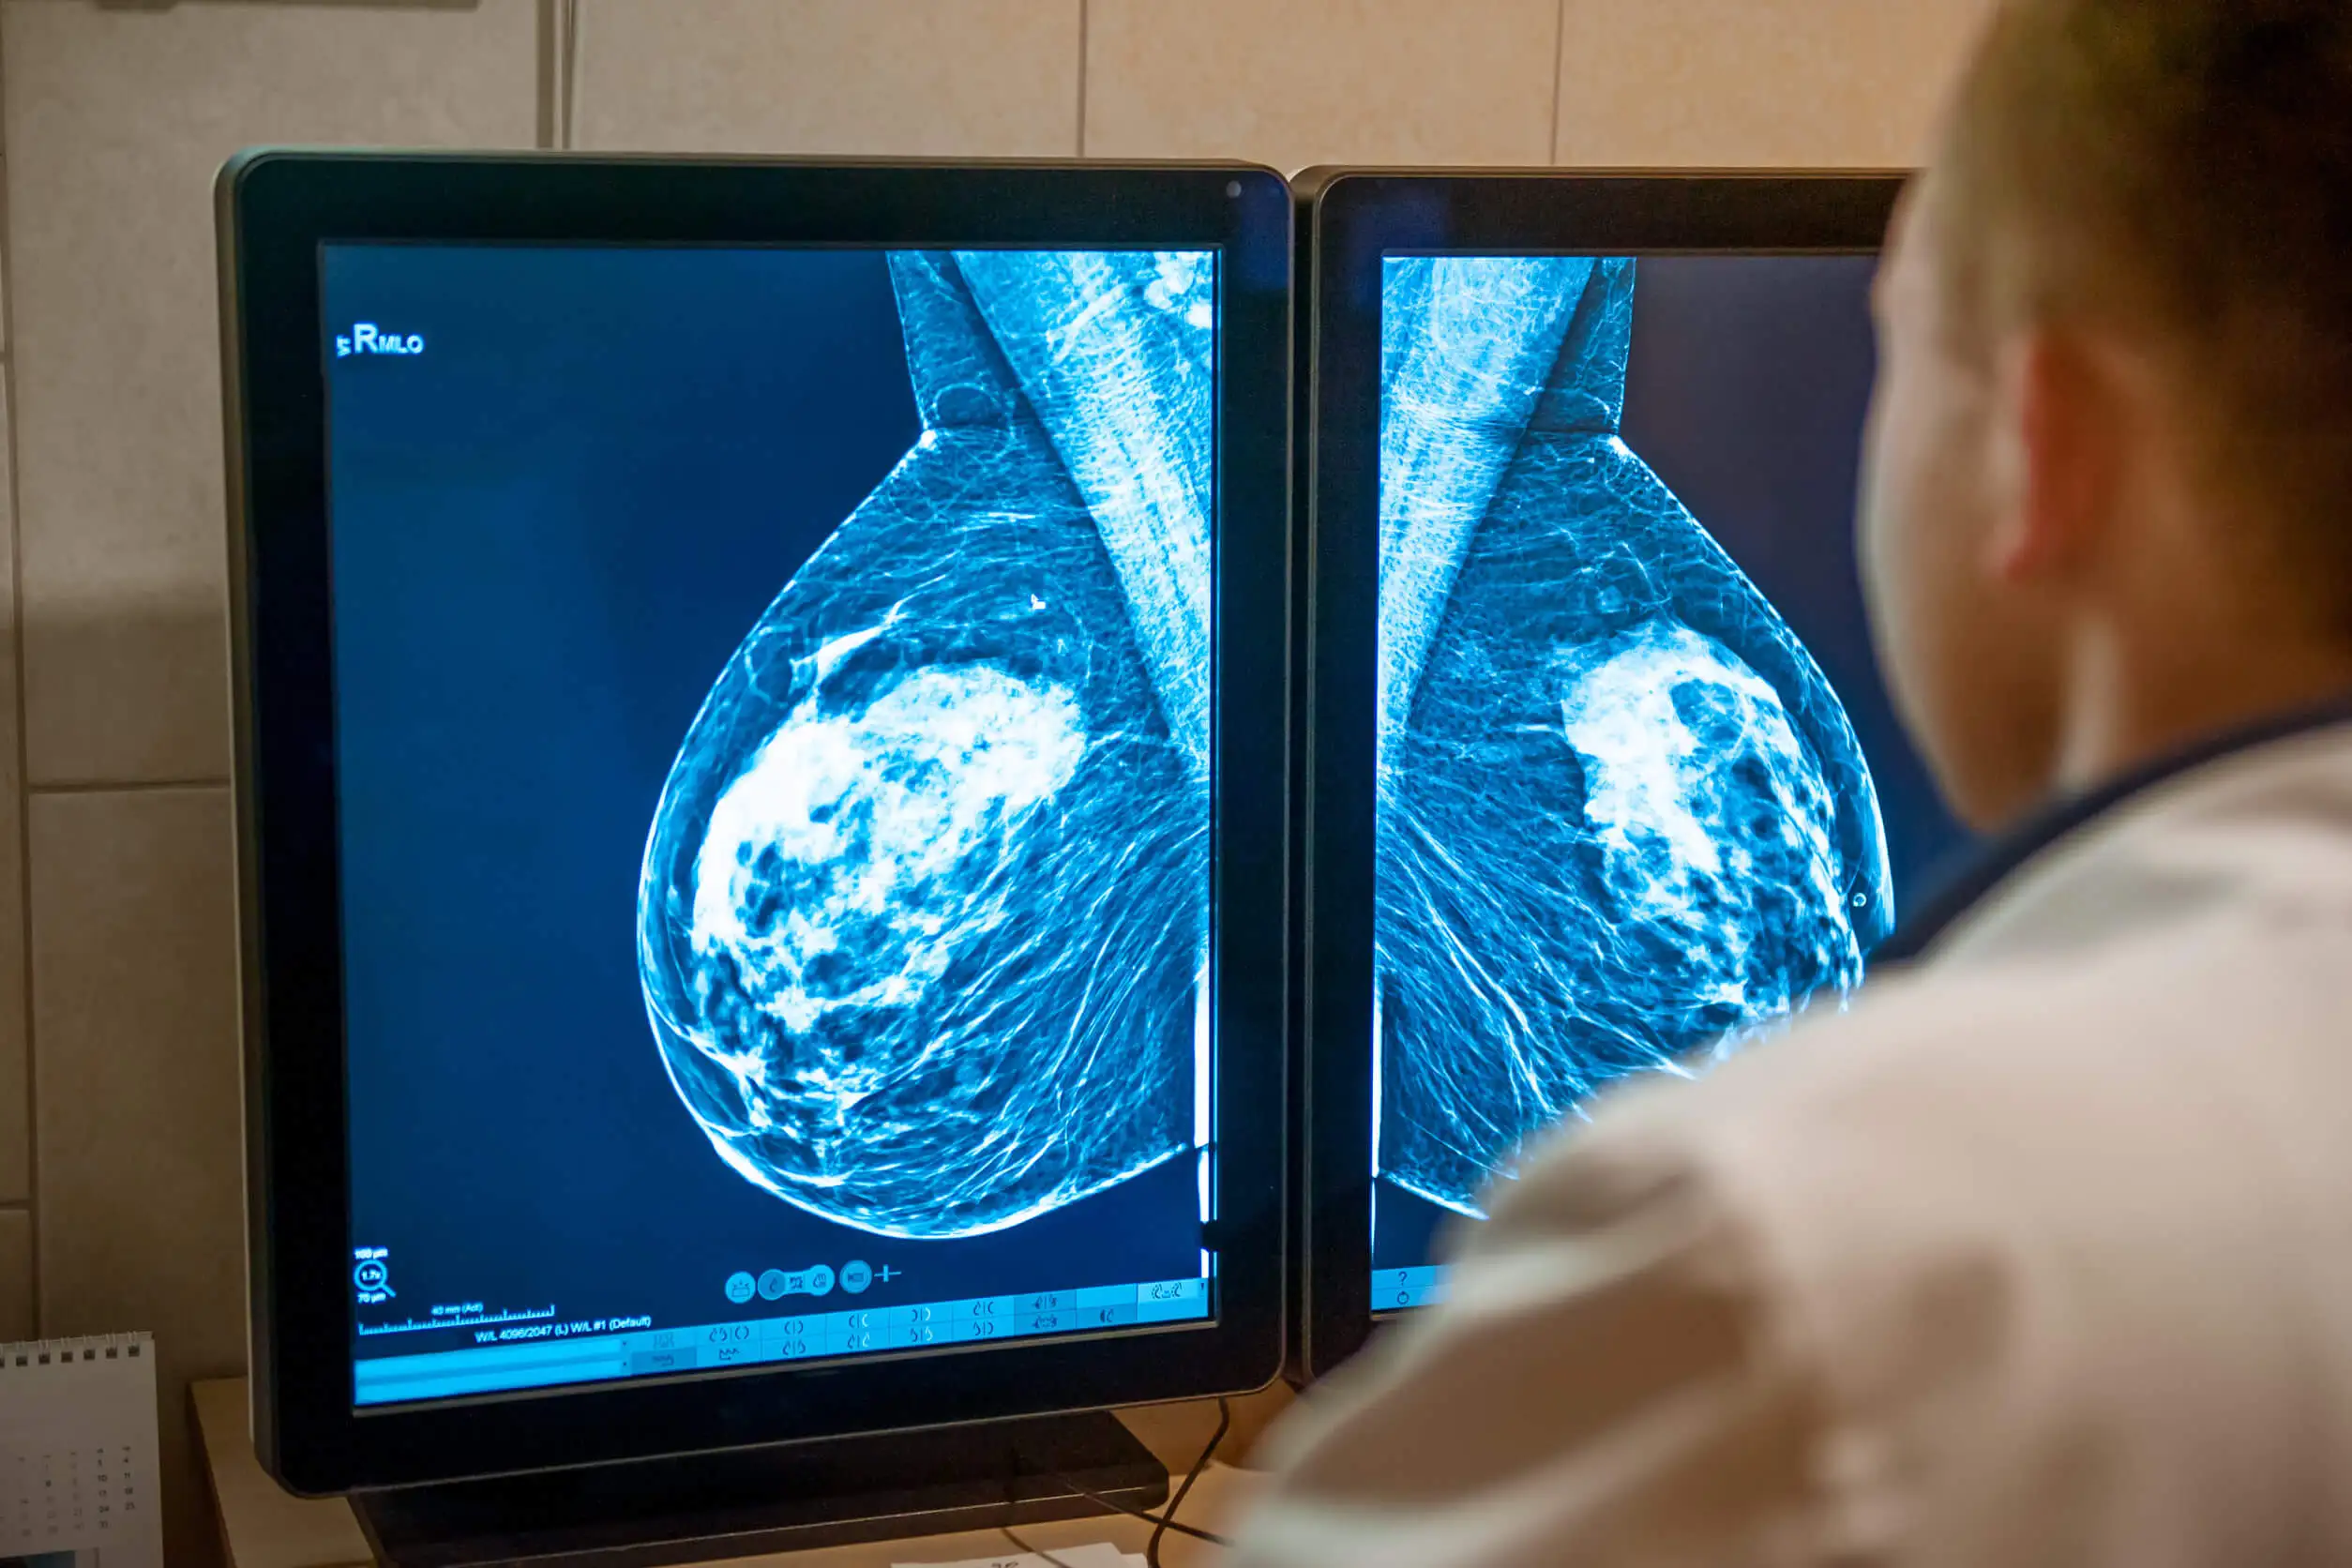

Vor der Behandlung sollte eine CT- oder MRT-Untersuchung erfolgen, um eine dreidimensionale Karte des Tumors zu erstellen. Dann berechnen die Onkolog/innen mithilfe von Computerprogrammen und spezieller Software, wie die Behandlung in der richtigen Dosis und an der richtigen Stelle verabreicht werden sollte.